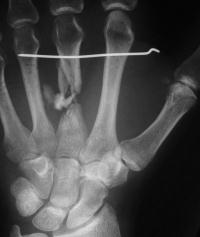

I believed that the nonunion was due to the combined effects of an avascular wound bed, segmental sclerotic bone, and the mechanical effect of cross union transferring force from the ring metacarpal to the distal metacarpal segment. I removed the broken plate,

debrided the sclerotic fracture site, took down the cross union,  interposed a second web space interosseous muscle flap to prevent recurrent synostosis, and used an iliac crest segmental graft carved with intramedullary dowel extensions.

I used the Synthes modular hand set, which has screw intervals different than the small fragment set.

This was the longest plate available, not optimum, but had six cortex purchase on each side of the graft.